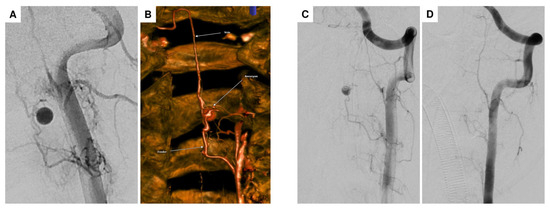

| 3 | F | 25 | acute headaches, complete tetraplegia, bradypnea, and asystole → cardiopulmonary resuscitation with ROSC | hypoesthesia on the left side at C6 and left thoracic and abdominal areas, left hemiparesis, tremor, and hemiataxia | spinal intramedullary aneurysm at C2 with perimedullary fistula | aneurysm | multiple DSA, multiple spinal MRI | surgical procedure (arterial feeder coagulation) |